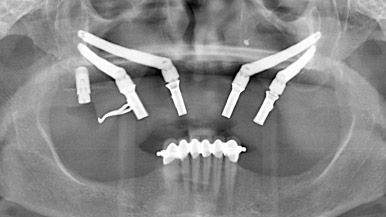

Zygomatic Dental Implants

Zygomatic dental implants are implants that are much longer than conventional implants (40 mm – 50 mm), and are placed in the dense Zygoma bone or otherwise known as the cheekbone. The advantage of using Zygomatic Implants is that it eliminates the need for procedures like ridge augmentation (Bone Grafting) and/or Sinus Lifting, which would require more surgery and longer healing periods before the placement of the final restoration.